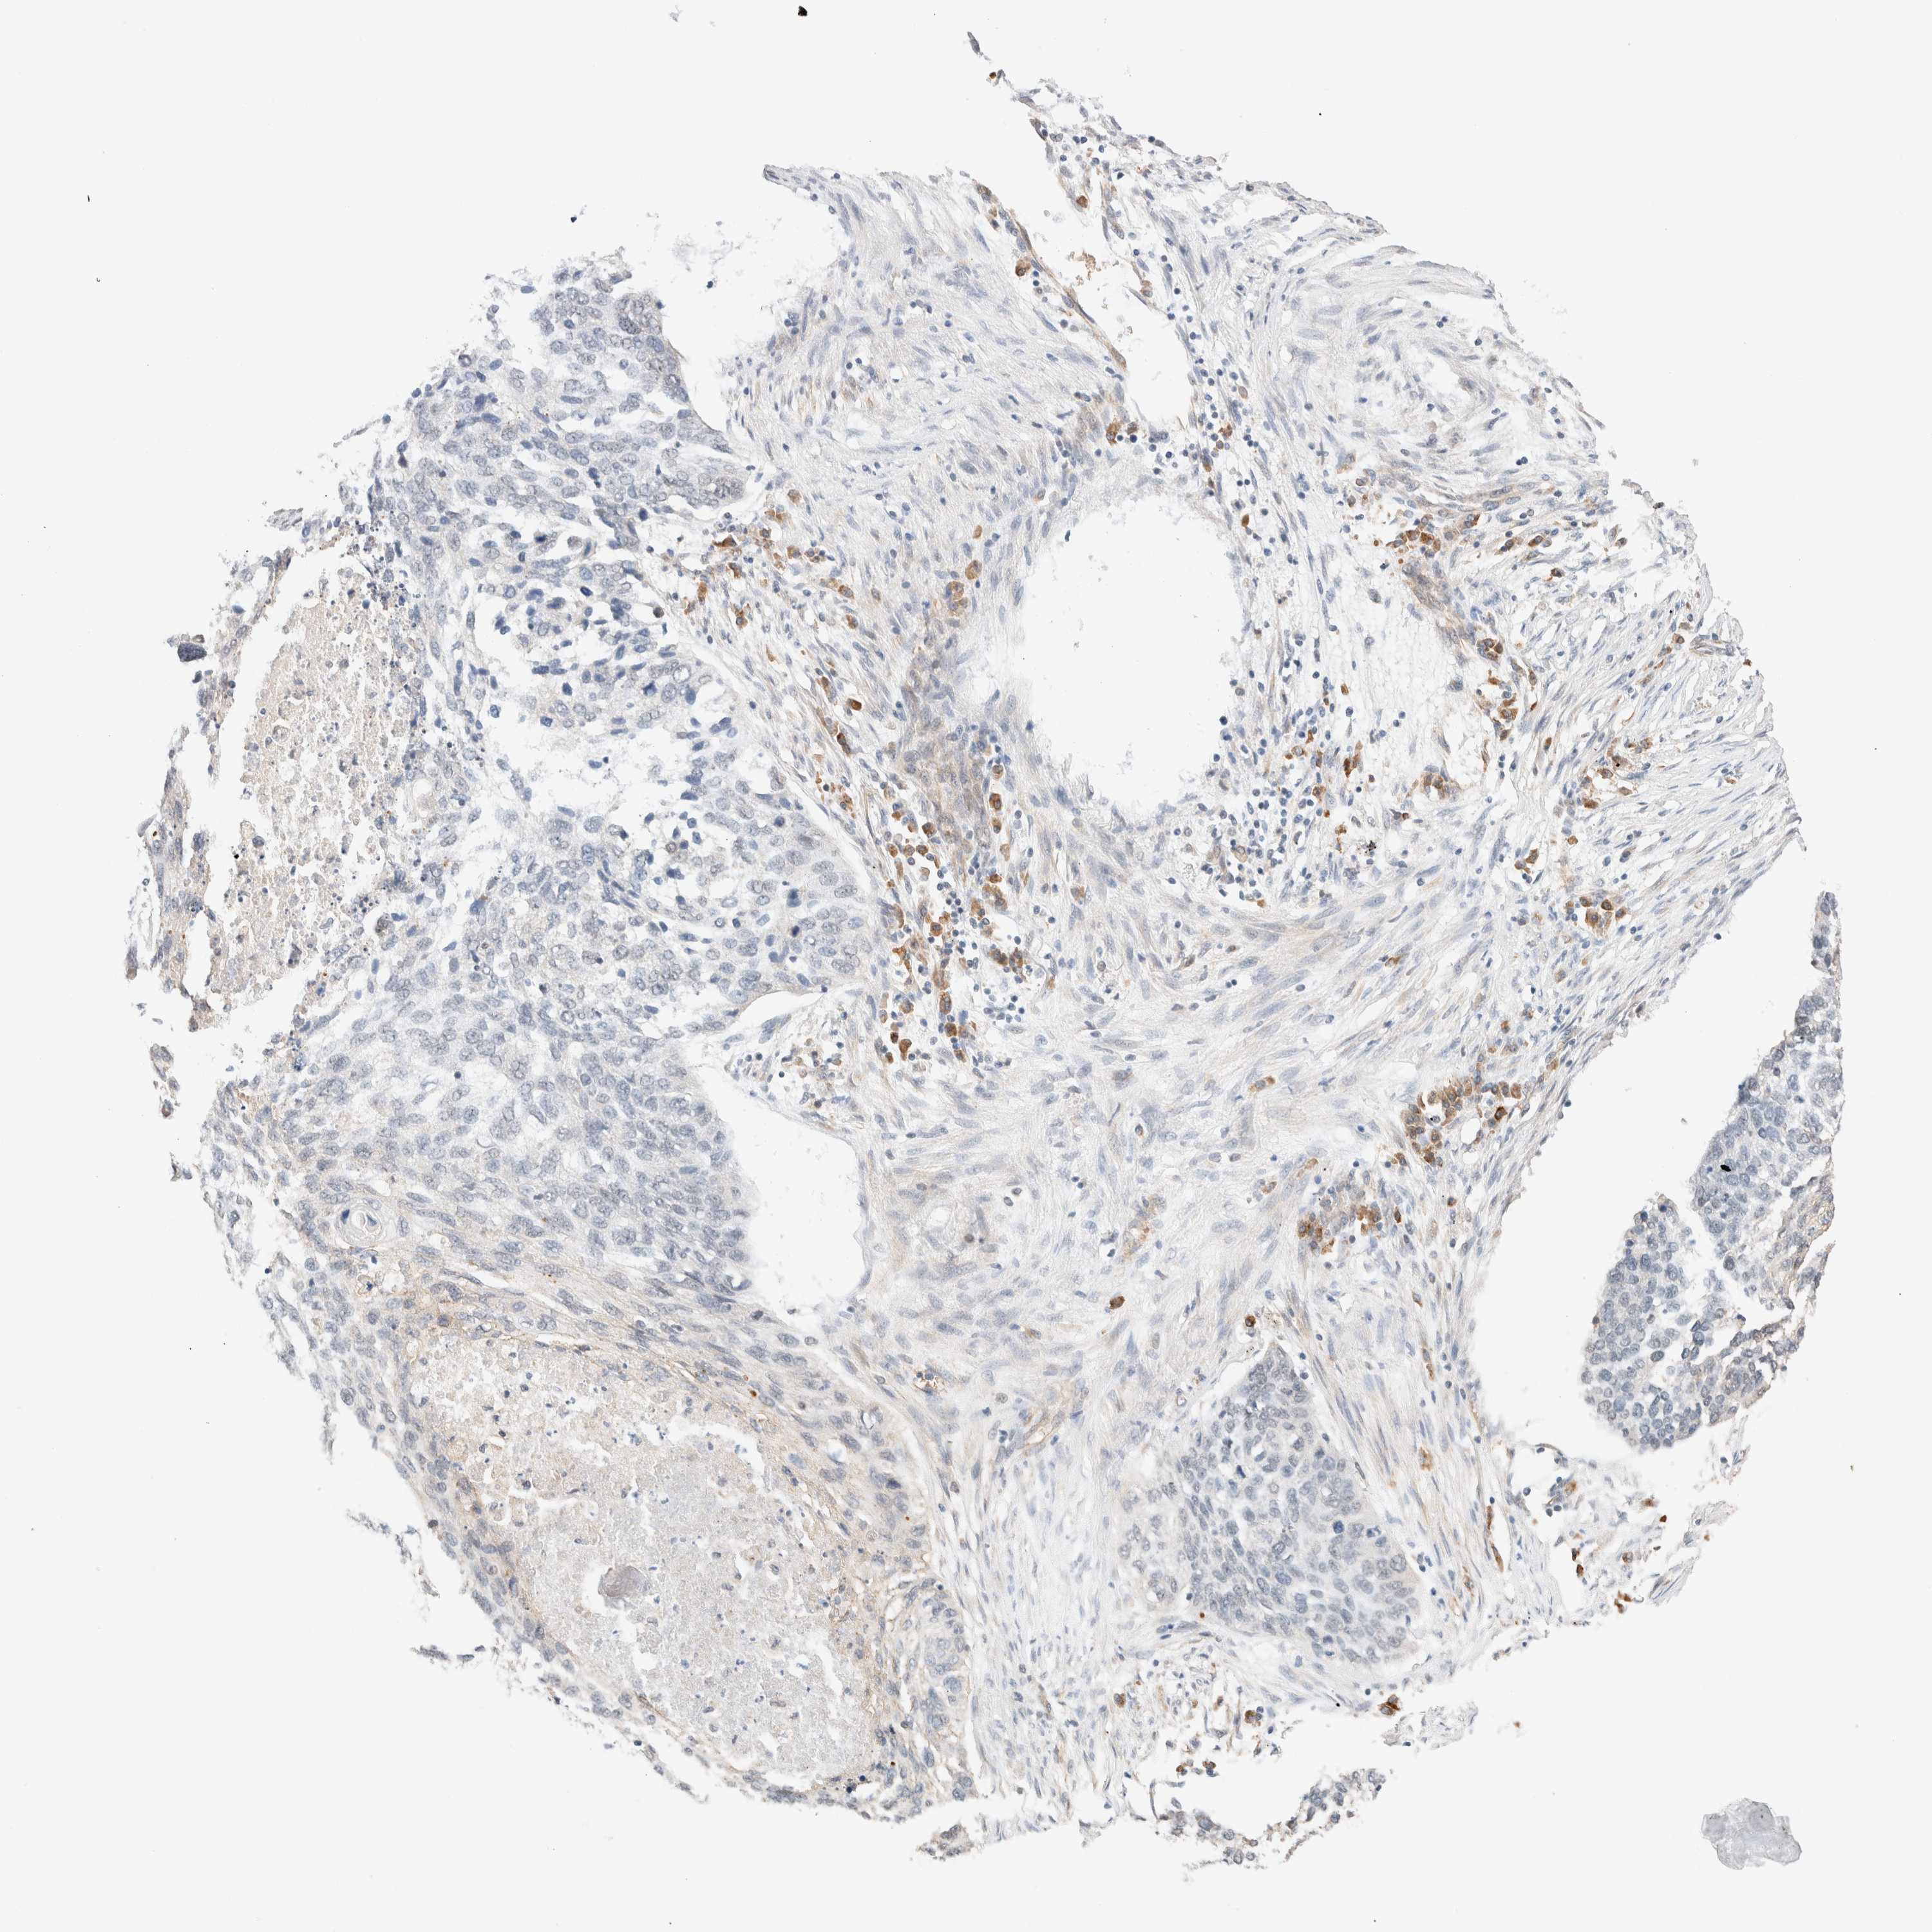

LUNG ADENOCARCINOMA (VALIDATION) - Interactive survival scatter ploti

The Survival Scatter plot shows the clinical status (i.e. dead or alive) for all individuals in the patient cohort, based on the same data that underlies the corresponding Kaplan-Meier plots. Patients that are alive at last time for follow-up are shown in blue and patients who have died during the study are shown in red.

The x-axis shows the expression levels (FPKM) of the investigated gene in the tumor tissue at the time of diagnosis. The y-axis shows the follow-up time after diagnosis (years). Both axes are complimented with kernel density curves demonstrating the data density over the axes. The top density plot shows the expression levels (FPKM) distribution among dead (red) and alive patients (blue). The right density plot shows the data density of the survived years of dead patients with high and low expression levels respectively, stratified using the cutoff indicated by the vertical dashed line through the Survival Scatter plot. This cutoff is automatically defined based on the FPKM cutoff that minimizes the p-score. The cutoff can be changed by dragging the vertical line or by entering a cutoff value in the square labeled "Current cut-off".

Under the Survival Scatter plot the p-score landscape (black curve; left axis) is shown together with dead median separation (red curve; right axis). Dead median separation is the difference in median mRNA expression between patients who have died with high and low expression, respectively. It is calculated as follows: median FPKM expression of dead patients with high expression - median FPKM expression of dead patients with low expression. This is intended to aid the user in visually exploring custom cutoffs and the associated p-scores and dead median separation.

Individual patient data is displayed and can be filtered by clicking on one or more of the category buttons on the top of the page. Categories describing expression level and patient information include: high, low, alive, dead, female, male and tumor stages. The scale of the x-axis can be toggled between linear and log-scale by clicking on the "x log" button. Mouse-over function shows TCGA ID, patient information and mRNA expression (FPKM) for each patient.

& Survival analysisi

Kaplan-Meier plots summarize results from analysis of correlation between mRNA expression level and patient survival. Patients were divided based on level of expression into one of the two groups "low" (under cut off) or "high" (over cut off). X-axis shows time for survival (years) and y-axis shows the probability of survival, where 1.0 corresponds to 100 percent.

SYVN1 is not prognostic in Lung Adenocarcinoma (validation)

: 44.62